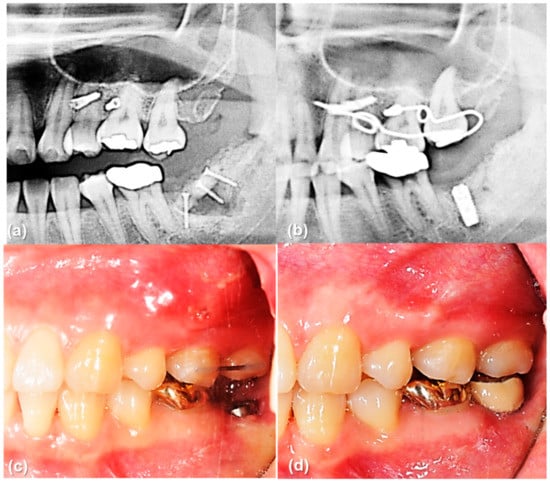

The main result of this study that the rotational resistance of the orthodontic miniscrew with a novel design was increased would be applied to the clinical situation where the increased moment is required. Figure 9 and Figure 10 shows an example of the counterclockwise rotational force applied to an orthodontic miniscrew. A patient with an extruded upper left second molar was treated by one of the authors (K.R.C). The patient agreed and signed an informed consent form that the authors would use photos for the publication of an article. In this case, the orthodontic wire used to intrude the extruded upper left second molar was inserted into a hole in the heads of both orthodontic miniscrews between the upper left second premolar and the upper left first molar on the buccal and palatal side of alveolar bone. On the buccal side, the wire generated a counterclockwise rotational moment on the orthodontic miniscrew. If the amount of moment had been higher than the rotational resistance of the orthodontic miniscrew, the orthodontic miniscrew would have been loosened and the intrusion of the upper left second molar would have failed. In this case, the osseointegration was effective enough to stabilize the orthodontic miniscrew under the heavy moment of the counter-clockwise rotation.

Figure 10.

The orthodontic miniscrew supported the counterclockwise rotational force in a patient with extruded upper left second molar: (a) Pretreatment panoramic radiograph shows extrusion of upper left second molar. (b) Posttreatment panoramic radiograph shows sufficient intrusion of upper left second molar after six months of treatment. Dental implant was placed in the lower left second molar area. (c,d) Intraoral photographs before and after implant crown treatment.